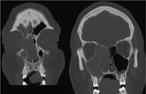

Ethmoid malformation associated with pediatric nasal polyposis and allergic fungal sinusitis

Cameron G. Hanson and Todd B. Proctor

Journal of Surgical Case Reports, Volume 2017, Issue 6, June 2017, rjx099, https://doi.org/10.1093/jscr/rjx099